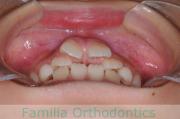

歯並びを治したいということで来院されました。下あごがやや右側に偏位して後退している、上顎前突(出っ歯)でした。上下左右から小臼歯を抜歯して、歯科矯正用アンカースクリューを併用したマルチブラケット法にて治療を行いました。約2年、24回の来院をしていただきました。

下顎の後退はいびきなどの上部気道の障害が出やすいと考えられます。

右側

正面

左側